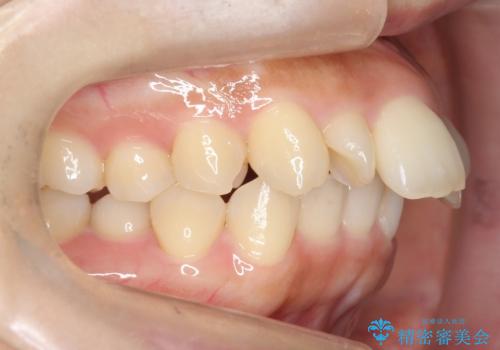

前歯がでている 最小限の抜歯で口を閉じやすく

- 出っ歯を主訴に来院。

上下のかみ合わせが1本分左右ともずれていました。